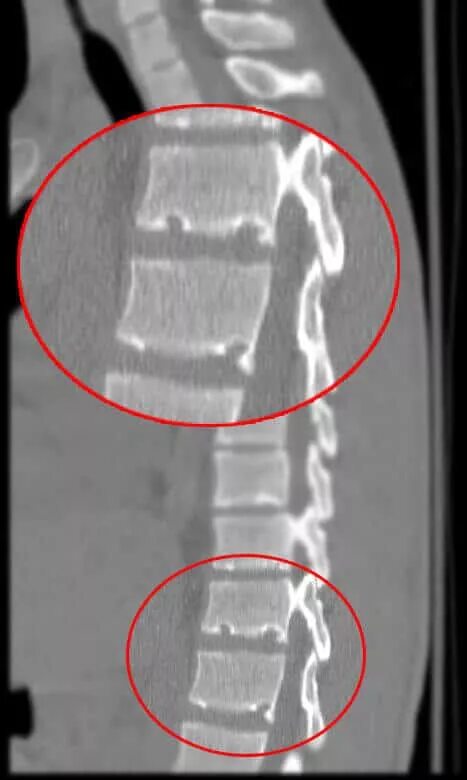

Что такое шморля в позвоночнике поясничном отделе